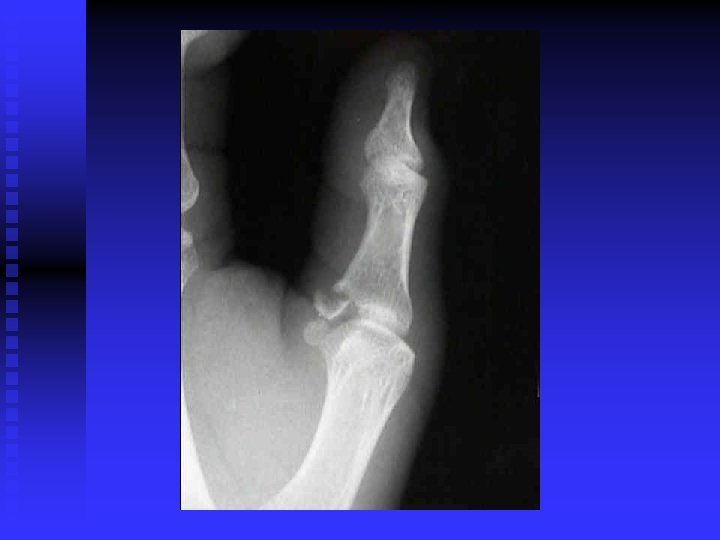

FINGER DEFORMITIES n n n n n Swan Neck Boutonniere Claw fingers Trigger finger Ape hand Bishops hand Dupuytren Contracture Mallet finger Gamekeepers Thumb